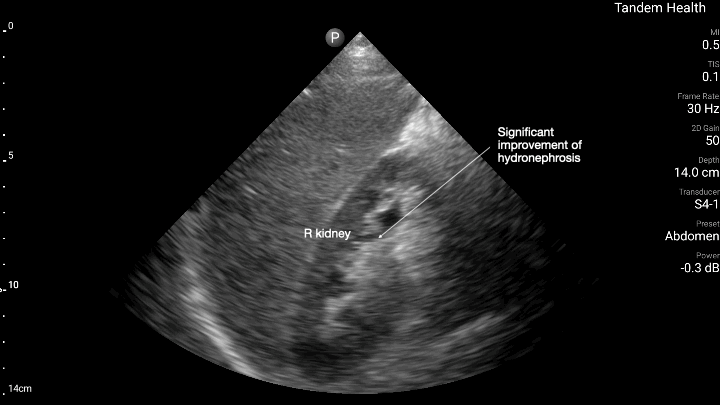

POCUS of his right kidney in clinic with foley in place showing improvement in obstruction.

Point of care ultrasound (POCUS) of the bladder and kidneys takes minutes to perform and would have revealed if he was retaining urine despite medical treatment years ago, and between his first and second hospitalization if his trial without foley had failed within those first 2 days when he wasn’t urinating. This highlights how POCUS could have potentially prevented long term kidney damage if complications are caught early.